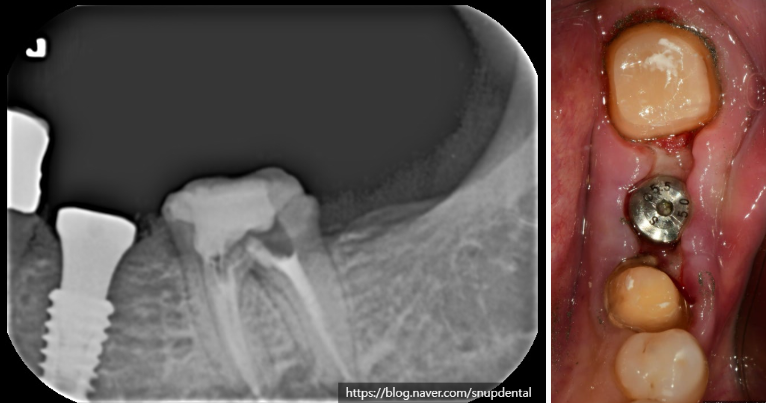

왼쪽 아래 브릿지 치아가 불편하다고 서울업치과에 내원하신 환자입니다

불편한 증상을 확인하고 어금니(#37) 부위에 문제가 있고, 작은 어금니(#35)는 살려 쓸 수 있다고 판단됩니다.

브릿지를 제거하고 어금니를 살펴보니 2차 우식이 진행되어 치아가 상당히 많이 연화되었고 치수강까지 진행되어 근관치료(신경치료)를 진행하기로 하였습니다.

또한 치아가 상실된 곳은 부착치은이 소실되고 협측골이 상대적으로 얇아졌으나 임플란트 치료하기에는 문제가 되지 않기에 임플란트 치료를 진행하기로 하였습니다.